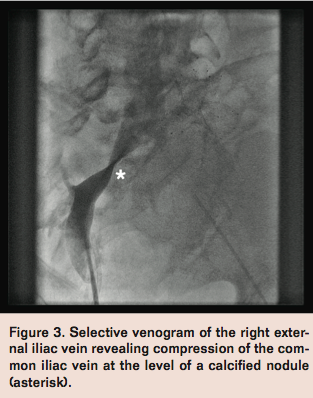

Venography via left popliteal vein access revealed a hazy filling defect in the left femoral vein. Selective venogram of the left external iliac vein was performed with the use of a glide catheter and revealed compression of the left common iliac vein at the level of the previously stented right common iliac artery (Figure 1). Intravascular ultrasound imaging of the left common iliac vein confirmed extrinsic compression (Figure 2), and identified the likely etiology of DVT.